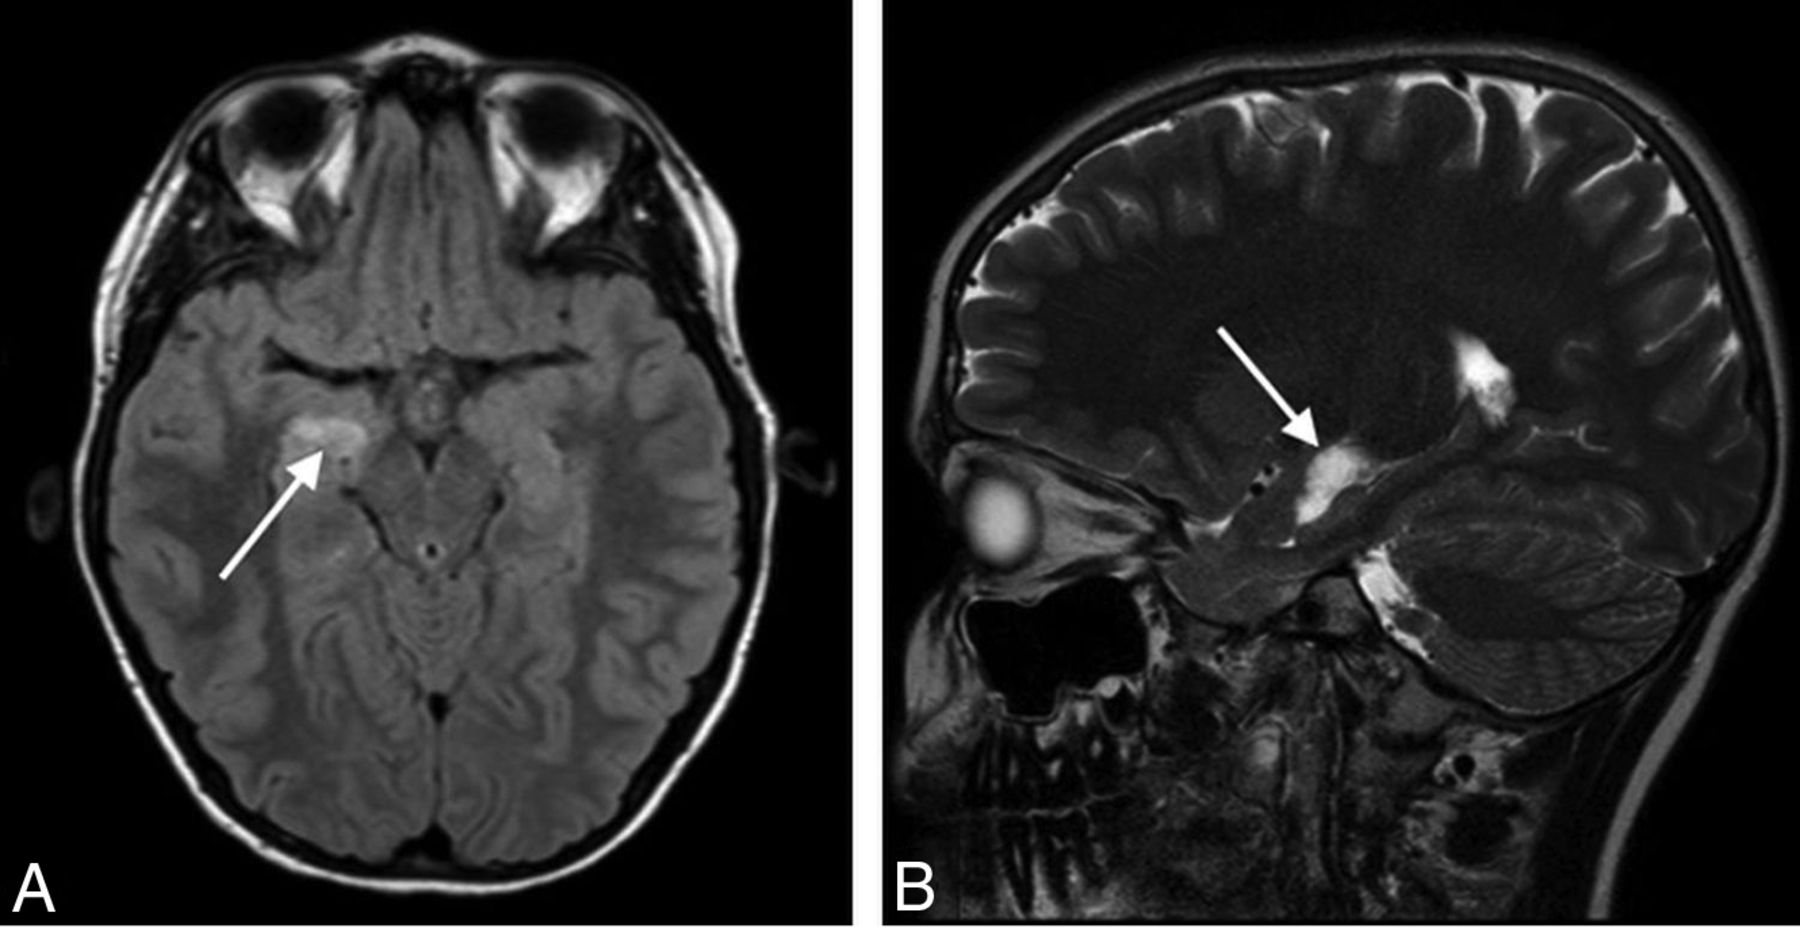

The 3 most common radiologic findings on the studies with abnormal findings were pars intermedia or Rathke cleft cyst (28%, n = 38), a subjectively small anterior pituitary gland (27%, n = 36), and an ectopic or absent posterior pituitary gland (15%, n = 20) (Table 2). A small anterior pituitary gland was determined via subjective assessment of the size/height of the anterior pituitary gland, taking known demographic characteristics (patient age and sex) into account. Microadenoma was identified or suspected in 9 cases (7%). Therapeutic decisions were unaffected by the presence of a suspected microadenoma in all cases. The 7 cases of hypothalamic region pathology included 2 cases of hypothalamic hamartoma, 2 cases of suprasellar arachnoid cyst, 1 case of hypothalamic glioma (Fig 1), 1 case of lipoma of the tuber cinereum, and 1 case of mass effect on the hypothalamus due to extra-axial fluid collections.

Sagittal T1WI of the sella (A) demonstrates a gray matter–isointense suprasellar mass lesion (arrow). Sagittal postgadolinium T1WI (B) shows enhancement, indicating a diagnosis of neoplasm (hypothalamic glioma) rather than hamartoma.